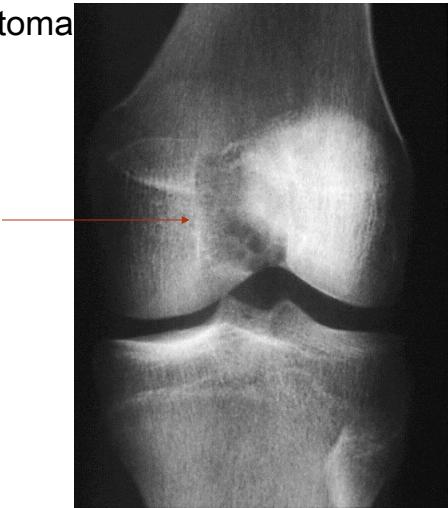

Giant Cell Tumor

Epiphyseal-Metaphyseal Lesions

Benign aggressive lesions:

- Giant Cell Tumor (GCT)

Aneurysmal Bone Cyst